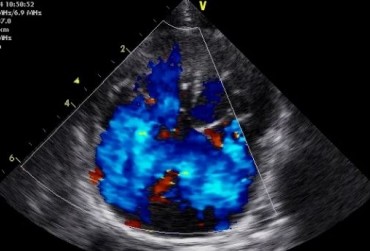

Badanie echokardiograficzne projekcja lewostronna koniuszkowa czterojamowa z Dopplerem kodowanym kolorem

19 lutego 2019

Urszula Bartoszuk